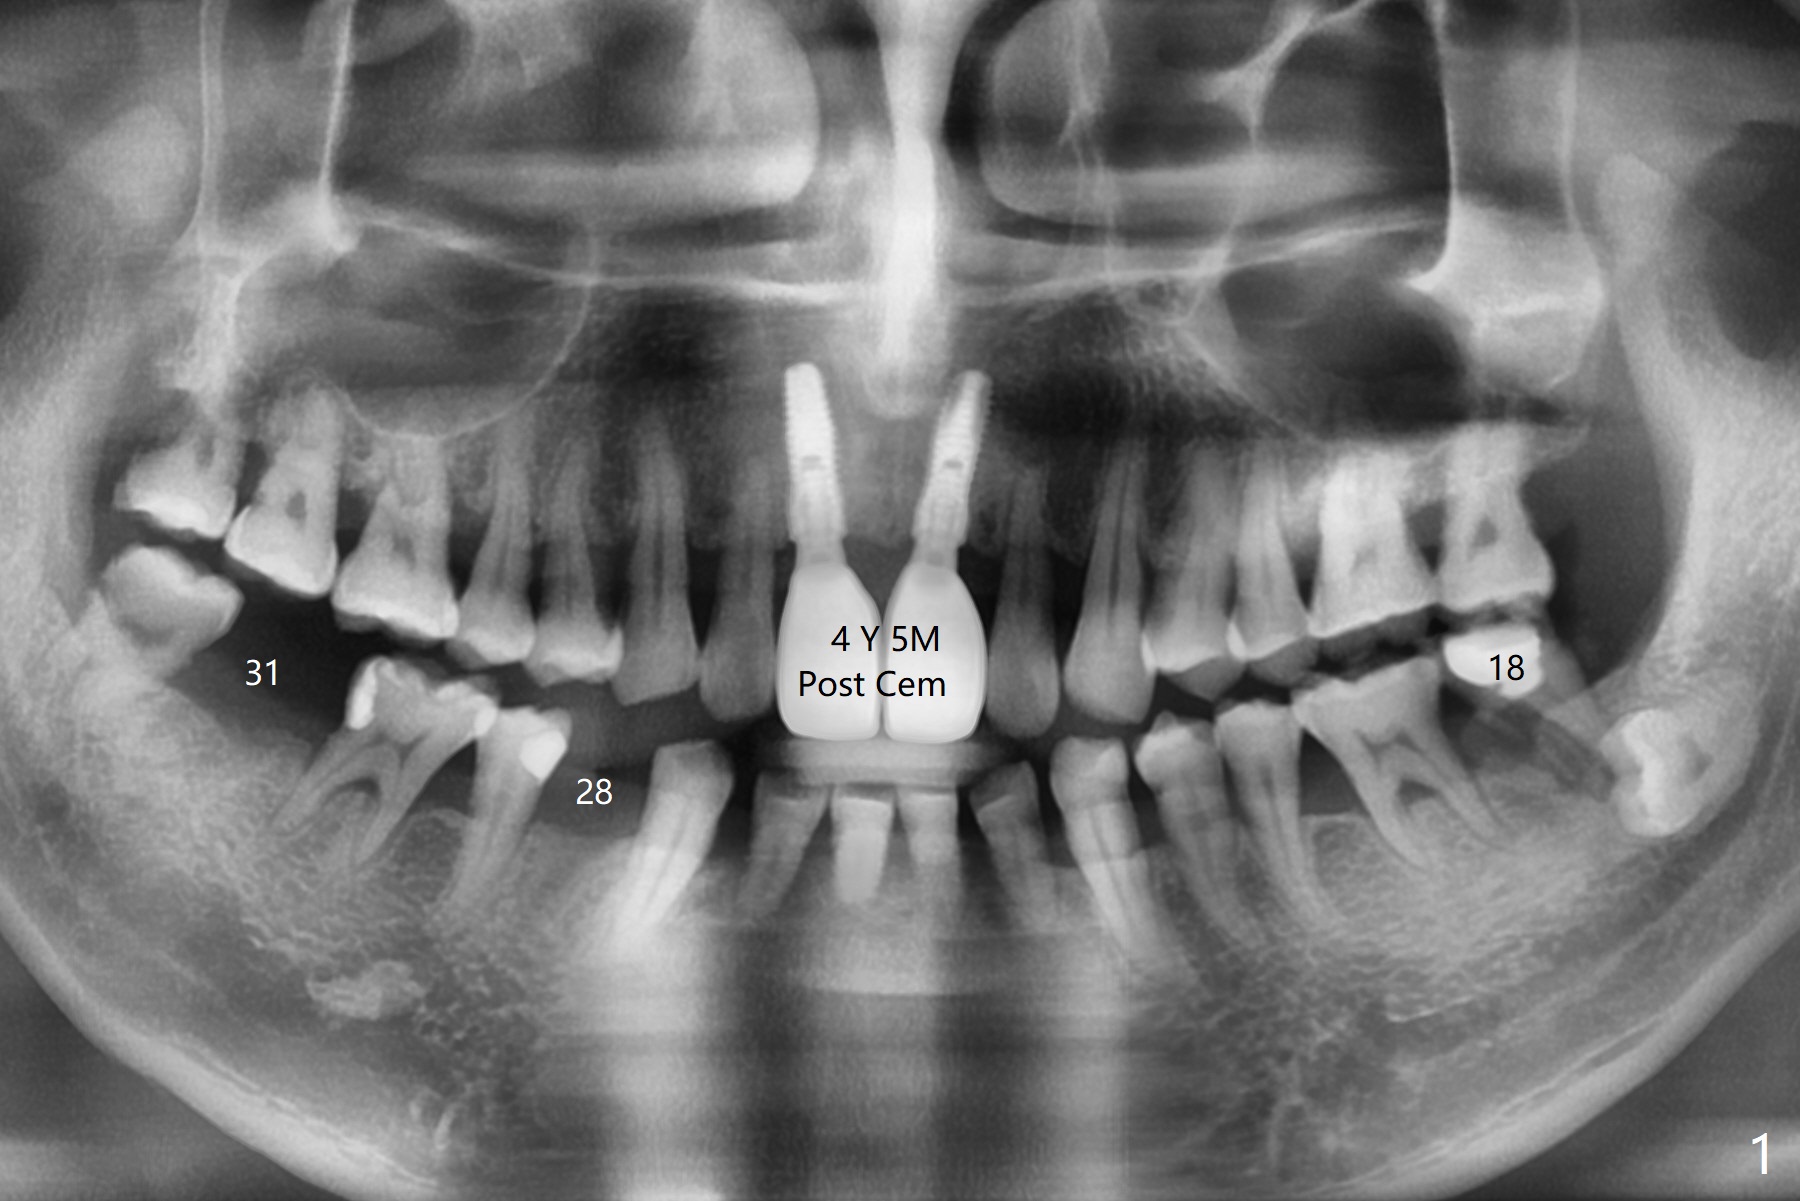

A 54-year-old man returns for #28 and 31 implants 3 months post extraction (#8,9 implants 4 years 5 months post cementation, Fig.1). The buccal plate at #28 is concave (Fig.2 *). After 2.2 mm drill to the depth as lingual as possible (Fig.3 L), use bone expanders through the guide to push the buccal plate out. Use Magic split or bone scalpels and blades to facilitate the expansion if needed. Place mixture of autogenous bone from #18 (Fig.4) and allograft buccally before implant insertion. Vertical fracture of the mesial root at #18 is an incidental finding (Fig.5 M). To avoid the impacted 3rd molar, osteotomy will be initiated as mesial as possible (Fig.6).